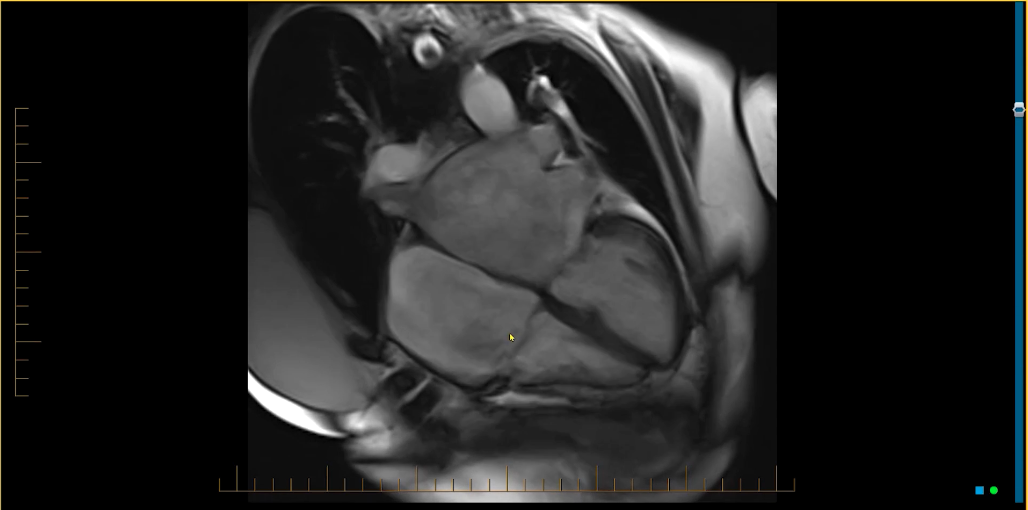

What is the likely cause of this patient’s heart failure symptoms?

Fine-tune your search patterns & work through your list of differential diagnoses with this challenging case from Dr. Stefan Zimmerman!